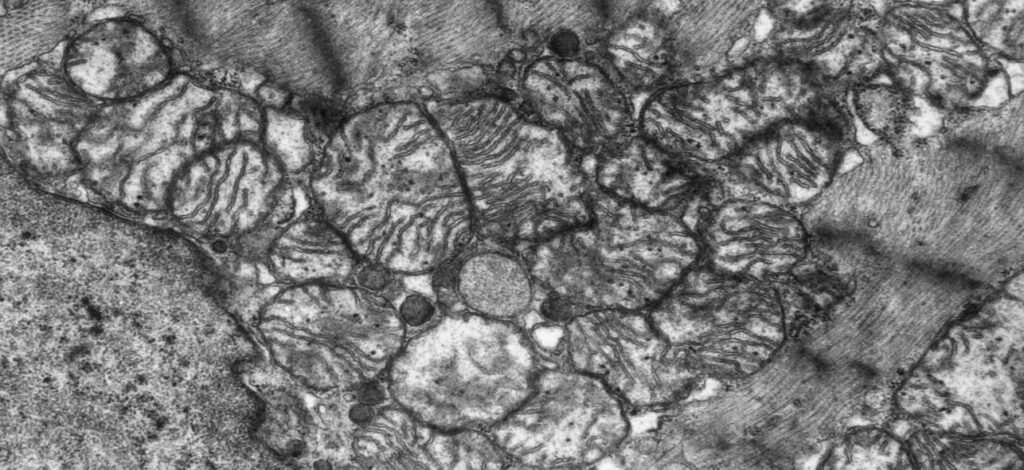

ミトコンドリア|エネルギーを産生する

ミトコンドリアが特徴的な構造を持つ細胞小器官です。

内膜と外膜の二重膜構造を持ち、内膜と外膜の間は膜間腔、内膜の内側はマトリックスと呼ばれます。

内膜では電子伝達系、マトリックスではTCA回路や脂肪酸のβ酸化が行われるため、それらに関与するシトクロムオキシダーゼなどの酵素を持ちます。

TCA回路や電子伝達系を介して多くのATP(エネルギー)を産生することができます。

また、ミトコンドリア独自のDNA(環状)とリボソームを持ち、必要なタンパクを合成や分裂を独自に行うことができます。

ミトコンドリアは電子顕微鏡写真もよく出てきます。

下のシマシマに見える部分がミトコンドリアです。